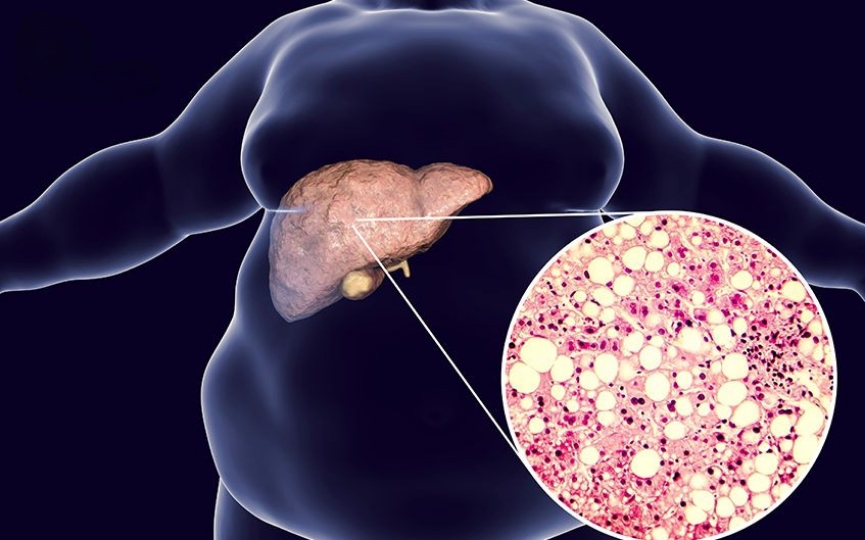

Tình trạng tích tụ mỡ hoặc chất béo trong tế bào gan được gọi là gan nhiễm mỡ. Viêm gan mạn và xơ gan không phát triển trong trường hợp gan chỉ nhiễm mỡ mà không có viêm. Bệnh gan nhiễm mỡ là một loại gan nhiễm mỡ gây viêm tại gan(Fatty liver disease).

Bệnh gan nhiễm mỡ có thể xảy ra do nguyên nhân là bia rượu, và nguyên nhân không phải do bia rượu hay còn gọi là viêm gan nhiễm mỡ không do rượu (Non – alcoholic fatty disease – NAFLD). Khoảng 30% những người nhiễm mỡ gan không do rượu sẽ bị viêm gan, có thể dẫn đến xơ gan và viêm gan mạn. Nhiễm mỡ thường không ảnh hưởng nhiều đến chức năng gan ở giai đoạn đầu. Tuy nhiên, theo thời gian, bệnh sẽ ngày càng nghiêm trọng và dẫn đến nhiều biến chứng nguy hiểm.